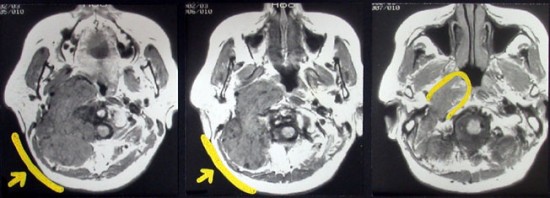

耳の聞こえと飲み込みが悪くなって発症(難聴と嚥下障害)した20代の患者さんのグロームス腫瘍 jugular paragangliomaです。左の頚動脈撮影 CAGでは,頸部の腫瘍におされて内頚動脈が前方に屈曲しています。外頚動脈から多くの血管が流入して血管腫のように濃い腫瘍陰影がみえます。右側の椎骨動脈撮影 VAGでは,頚静脈孔から頭蓋内の小脳延髄角部まで伸びた腫瘍が染まります。頭蓋内はPICAから頸静脈球と頸部には椎骨動脈の筋肉枝からの腫瘍血管がみられます。

頸部から頸静脈球を抜けてS上静脈洞内に入ります。これはクラスCかDか迷うところです。ちょっと難しい。またこのサイズでは,迷走神経と舌咽神経の機能を温存することができません。延髄方向へ伸展していますし年齢が若いので手術せざるを得ないものでした。

この腫瘍は放射線治療で制御できるものではないでしょう。手術で全摘出できて10年以上再発はありません。嚥下障害と強い嗄声が残りましたが,働いて社会生活はできています。